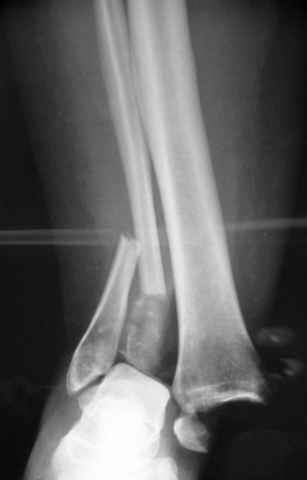

Re: ANKLE FRACTURE

Второй случай сделан из одного разреза